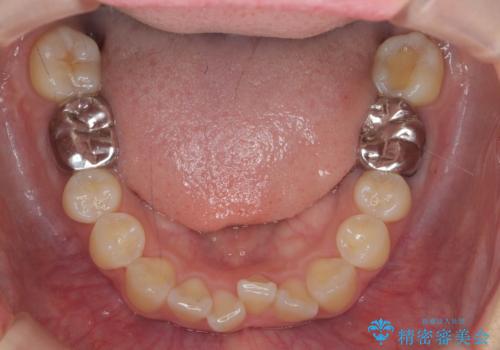

- 噛んだ時の前歯正中のズレ、引っ込んでいる前歯を治したい。と矯正治療を希望され来院されました。

左上2の前歯はスペースが足りないため、後方に引っ込んでしまっている状態です。

マウスピース矯正システムインビザラインで歯の後方移動、咬合関係の修正を行ったのち、引っ込んでいる左上2をワイヤーを用いて短時間で引き出す治療計画としました。